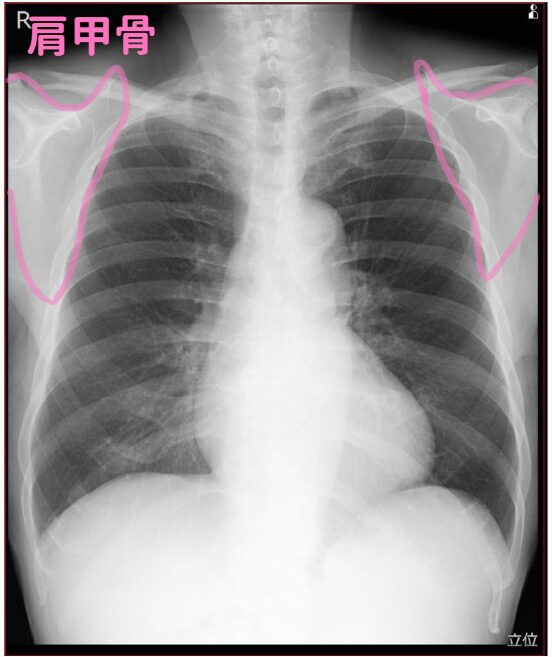

(2)肩甲骨

次に見ているのは肩甲骨です。

職員健診でレントゲンを撮る時を思い出して欲しいのですが、

レントゲンの板に抱きつくような体勢で撮影しますよね。

これは両腕を広げて、肩甲骨が肺野に入らないようにしているんです。

ポータブルレントゲンでは肩甲骨と上肺野が重なってしまうので、

肺がんを見逃さないように注意力をアップして見ています。